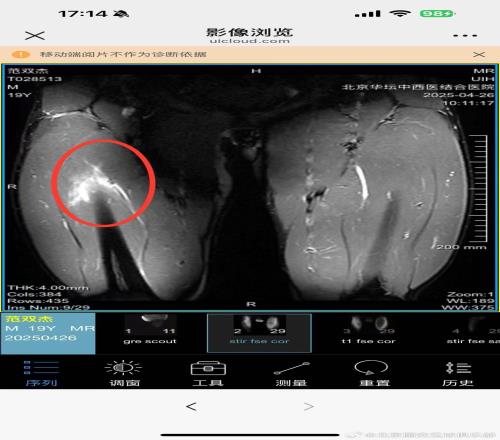

范双杰,4.25日主场对阵河南俱乐部酒祖杜康的比赛中,球员上半场比赛中左大腿受伤。伤后经核磁共振检查,显示左大腿缝匠肌肌腱拉伤,左大腿股直肌股外侧肌拉伤Ⅱ°。

目前症状:左大腿抬高疼痛4级(0-10)、行走痛4级、跑跳疼痛6-7级,髋膝关节灵活度优其他正常。